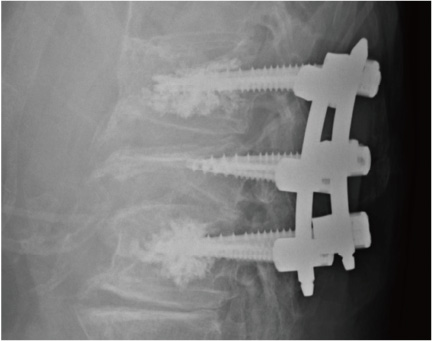

神経症状が出現した圧迫骨折については、残念ながら、BKP、VBSは適応ではありません。その場合には、神経症状改善のために、骨を削り神経への圧迫を取り除く必要があります。前方には骨折を起こした骨、 後方は神経の圧迫をとるために削る。それにより、脊椎は不安定な状態となります。 以前は、除圧部位の上下それぞれ2椎体ずつのねじで固定 をしておりましたが、最近はねじの先端からセメントが出るものがでてきており、椎体骨折の上下1椎体ずつの固定を行い、固定範囲を短縮させる試みを行っています (図2)。現時点では、ねじのゆるみもなく、順調に経過しています。